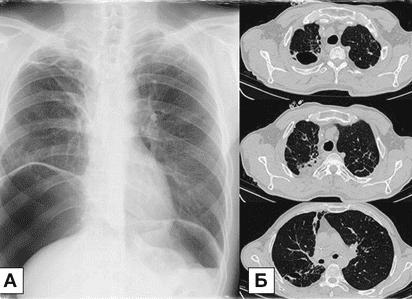

Что показывает КТ легких? Полученные томограммы достаточно хорошо визуализируют бронхи, доли и сегменты легких, трахею, . Снимки отображают состояние аорты, легочной артерии, сердца, верхней полой вены; можно отличить крупные туберкулезные очаги от опухолей, обнаружить бронхоплевральный свищ или эмфизему, отличить их от абсцесса. В случае обнаружения опухолей можно установить их природу, локализацию и размеры, распространение на другие органы.

Что можно увидеть на послойных снимках КТ

Данная методика позволяет диагностировать опухолевые процессы и их распространение в органах, патологию лимфатической системы — увеличение и изменение плотности узлов, воспалительные процессы в легочной и плевральной тканях, обструкцию и сужение бронхов, легочной артерии, верхней полой вены, аорты.

Кроме того, на снимках КТ прекрасно видно рубцы от перенесенной пневмонии или туберкулеза, тромбы в крупных сосудах, жидкость в плевральных полостях, врожденные аномалии в строении органов. У пациентов, занятых на вредных производствах, часто обнаруживаются профессиональные болезни легких, такие как силикоз, асбестоз и другие.

В органах средостения при обследовании могут быть диагностированы: загрудинный зоб, воспаления и дивертикулы перикарда, гнойные воспаления тканей грудной полости, сердечные болезни различной этиологии, аневризмы аорты , опухоли и расширение пищевода.